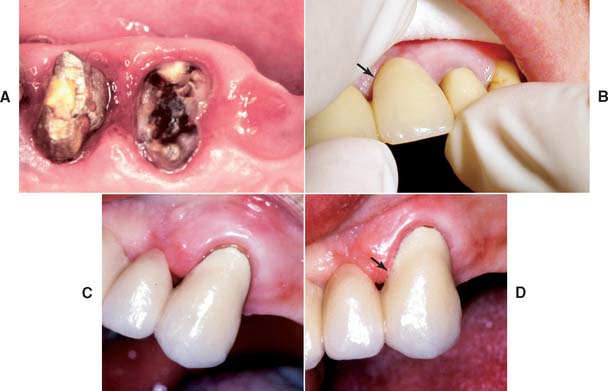

Dental caries (Fig. 32-8) is the most common cause of failure of a cast restoration.9-12 Detection can be very difficult,13 particularly where complete coverage is used. At each appointment, the teeth should be thoroughly dried and visually inspected (Fig. 32-9). The explorer must be used very carefully when early enamel lesions are assessed, because a heavy-handed examination may damage the fragile demineralized enamel matrix. An intact enamel matrix is essential for procedures that induce remineralization14 (e.g., improved plaque control, dietary changes, topical fluoride applications).

Fig. 32-8 Undetected caries beneath this partial fixed dental prosthesis resulted in serious complications.